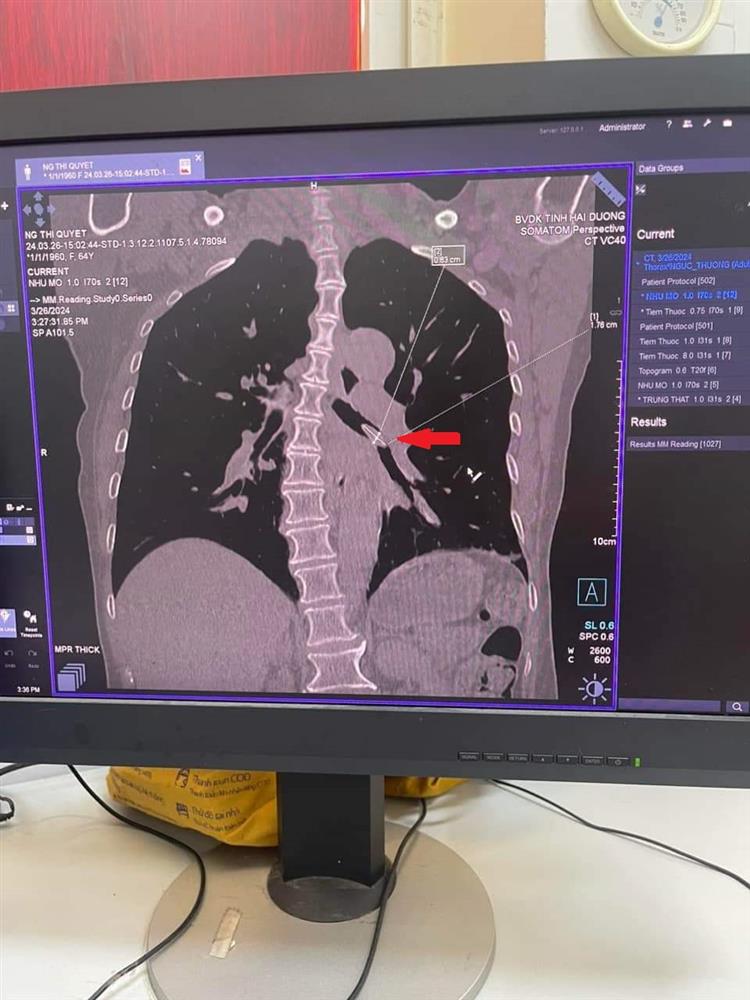

Bệnh nhân nữ 64 tuổi vào viện vì ho kéo dài 3 tháng, kèm theo tức ngực, cảm giác khó thở, cò cử. Bệnh nhân đã khám và điều trị tại TTYT huyện 2 đợt nhưng không đỡ. Tại khoa Hô hấp - Bệnh viện đa khoa tỉnh Hải Dương, bệnh nhân được chỉ định chụp CLVT lồng ngực có dựng hình cây khí phế quản, phát hiện dị vật ở 1/3 trên phế quản gốc trái. Bệnh nhân được chỉ định nội soi phế quản lấy dị vật. Sau 60 phút nỗ lực của ekip nội soi, dị vật là hạt hồng xiêm dài > 2cm đã được lấy ra khỏi phế quản. Bệnh nhân được xuất viện sau 5 ngày điều trị

Hình ảnh dị vật PQ gốc trái